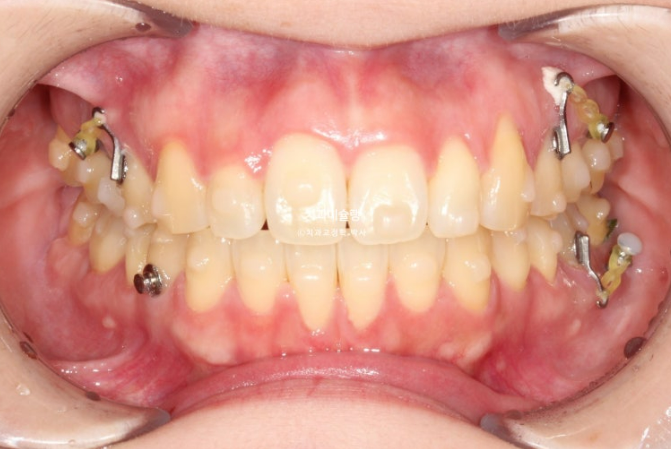

25년 6월, 1년간 첫세트의 50개 장치를 모두 낀 후 모습입니다.

25.06

중심선이 아직 어긋나 있지만 개방교합은 해소가 되었습니다.

교합관계는 1급이지만 어금니 교합이 약간 떠있습니다.

배열은 좋습니다.

미진한 부분을 바로잡고자 추가장치 재제작에 들어갑니다.